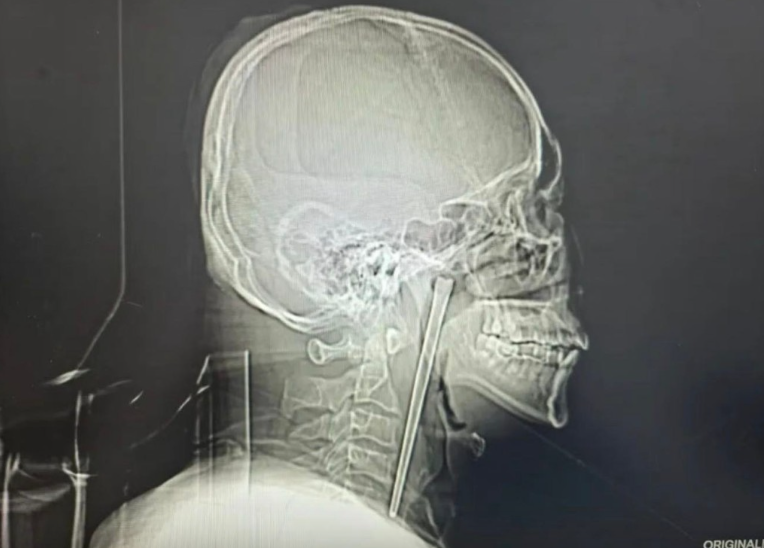

A 46-year-old man in Dalian, China, lived with a 12cm metal chopstick in his throat for eight years.

During the examination, medical staff were shocked to discover a 12cm metal chopstick lodged in his throat.

The man revealed that the chopstick had been in his throat for eight years.

Upon examination, doctors found the metal chopstick embedded in the posterior wall of his right pharynx, with about 3cm exposed.

Fortunately, the chopstick had not caused significant ulceration or bleeding.

His vocal cord movement was normal, and the laryngeal cavity structures had not been compressed or displaced.

Taking into account Mr Wang’s fear of major surgery, doctors devised a minimally invasive procedure to remove the chopstick.

The operation was a success, and the chopstick was removed fully intact.